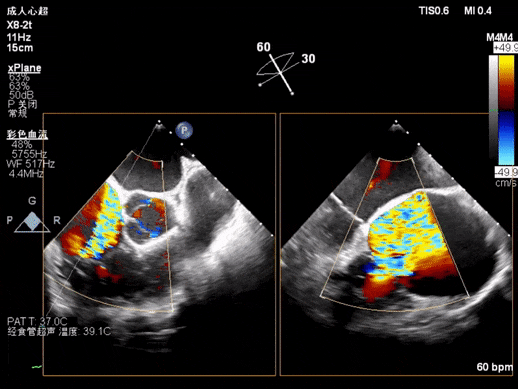

术后即刻评估,术中完成第二组锚片植入后,患者三尖瓣反流程度降至2+左右,三尖瓣反流量由128ml下降至16ml,有效反流口面积(EROA)由1.24cm²下降至0.26cm²,瓣环面积减少53%,三尖瓣反流改善明显,冠脉血流未见显著影响。

术中器械植入前

术中器械植入后